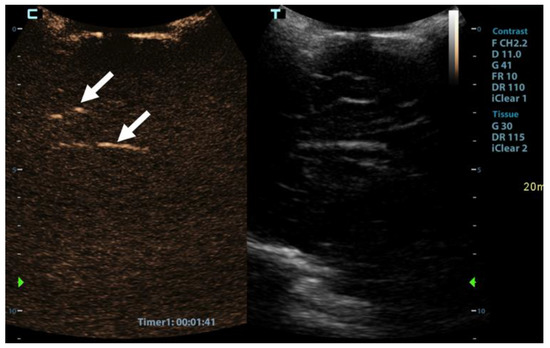

A 1-year-old girl, involved in a traffic collision, was found asystolic with dilatated and nonreactive pupils. The paramedics immediately initiated cardiopulmonary resuscitation, and the patient was transferred to the nearest hospital. At arrival, the girl was still unconscious and asystolic. After 20 min, cardiac action was re-established. On physical examination, numerous wounds and contusions were found on the patient’s head, and bleeds from the nose and ears were observed. Additional contusions were noted on the trunk and extremities. The girl did not react to painful stimuli and had a Glasgow coma scale assessment score of 3. A complete blood count showed low haemoglobin (80 g/L) with elevated serum lactate levels (14 mmol/L). Whole-body computed tomography (CT) was performed forthwith. A head CT disclosed several fractures of the frontal and occipital bones, bilateral subarachnoid haemorrhage in the frontal region, and massive haemorrhage in the right maxillary sinus. No changes were noted in the cervical spine. CT of the chest and abdomen showed multiple contusions of the lungs and haematomas in the mediastinum and right inguinal region. For the treatment of severe hypotension (45/35 mmHg), the patient received blood transfusions, norepinephrine, and dopamine. The patient was transferred to a tertiary hospital centre. As intracranial hypertension (ICP = 40 mmHg) was persisting, treatment with mannitol and analgosedation was initiated. Therapeutic hypothermia was not induced due to the presence of coagulopathy. A follow-up CT scan of the head was performed approximately 12 h after the accident and showed marked cerebral oedema with completely displaced ventricles. The subarachnoid haemorrhage was more extensive, and pronounced transtentorial herniation through the foramen magnum was noted. CT brain angiography disclosed absent blood flow within the cerebral arteries (Figure 1). The patient’s condition continuously deteriorated despite intensive treatment. Due to the poor prognosis, it was decided that further treatment was not feasible, and formal tests to confirm brain death were conducted.

Figure 1. Axial 3-mm-slab maximum intensity projection of the brain computed tomography angiography (CTA) of the 1-year-old infant. The CTA images (a,b) demonstrate absent contrast opacification of the intracranial arteries. Note the normal opacification of the extracranial arteries (arrows).